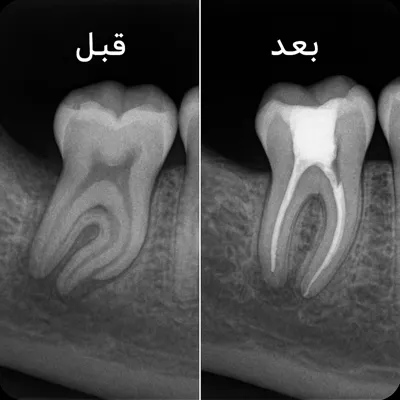

سپس با گرفتن رادیوگرافی تکدندان (PA) یا در صورت نیاز تصویر Bitewing، نواحی پوسیده، ترکهای سطحی یا نفوذ پوسیدگی به لایههای زیرین دندان مشخص میشود.

برای اطمینان از اینکه پوسیدگی هنوز به عصب دندان نرسیده، تستهای تشخیصی مانند تست گرما و سرما و تست دق (ضربه آرام به دندان) انجام میشود.

پاسخ دندان به این محرکها، به دندانپزشک کمک میکند تا بین حساسیت سطحی و التهاب عصب تمایز قائل شود.

در نهایت، با تفسیر نتایج این تستها و بررسی گرافی، تشخیص قطعی علت درد دندان موقع خوردن شیرینی صورت گرفته و درمان مناسب — از ترمیم ساده تا درمان ریشه — انتخاب میشود.

تشخیص زودهنگام در این مرحله اهمیت زیادی دارد، زیرا درمان پوسیدگیهای اولیه معمولاً ساده، سریع و کمهزینه است و از گسترش آن به عصب جلوگیری میکند.